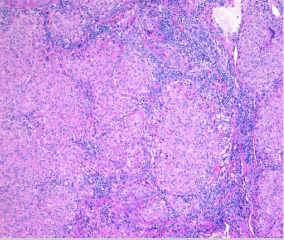

Sarcoidosis manifests as _______ on pathology

Sarcoidosis manifests as well-formed non-caseating granulomas on pathology